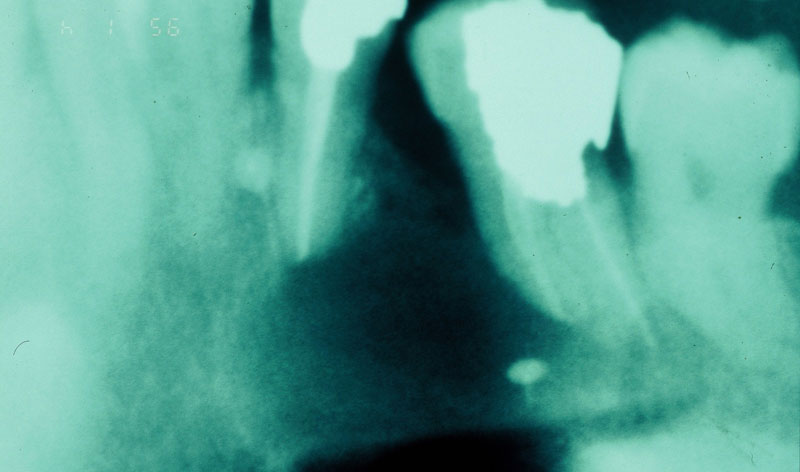

Es una intervención sencilla, que se asocia a la colocación del implante en los casos en los que el hueso no es lo suficientemente ancho como para que el implante quede rodeado por el mismo en su totalidad.

En algunos casos se regenera en el momento de la extracción del diente, para preparar mejor el hueso, dejándolo cicatrizar durante un tiempo hasta la puesta del implante. En otros, es en el momento de la colocación del implante cuando recurrimos a la regeneración del hueso perdido.